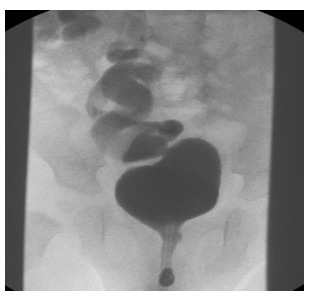

Figure 1: MCUG showing duplex system on the right side with Grade 4 VUR in the lower moiety ureter. Reflux is also demonstrated in the distended right upper moiety ureter.

The lower pole ureter is normally placed and usually associated with VUR, while the upper pole ureter is ectopic and most commonly associated with ureteroceles. The upper moiety ureters are usually obstructed with the ureterocele, however, in some cases can be associated with VUR as well [Figure 1].

Direct examination during cystoscopy can reveal more than one ureteric orifice on one side and thereby suggest a duplex renal system. MCUG can also reveal ureterocele and is commonly used [Figure 2].